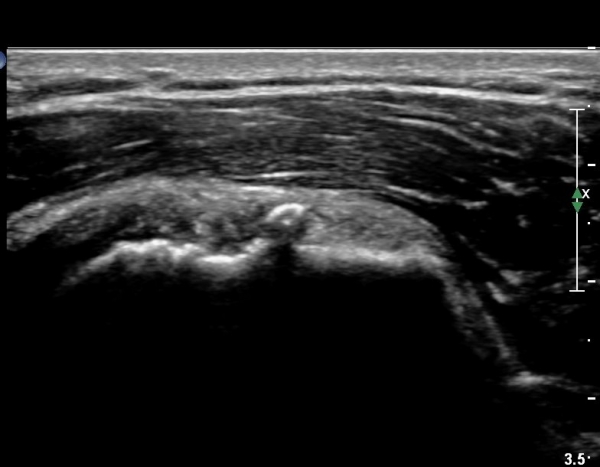

ÃÊÀ½ÆÄ ¼Ò°ß :  ÀÌµÎ¹Ú±Ù°Ç È¾´Ü¸é°Ë»ç¿¡¼­ ¼Ò°áÀý ºÎÂø °ß°©Çϱٰdz» °í¿¡ÄÚ ¼®È¸È­ µ¢¾î¸®°¡ °üÂûµÈ´Ù(»çÁø 1).

°ß°©ÇÏ±Ù°Ç È¾´Ü¸é°Ë»ç»ó ¼Ò°áÀý ÇÊÁú°ñº¯È­¿Í °ß°©ÇÏ±Ù°Ç Áߺο¡ °í¿¡ÄÚ µ¢¾î¸®°¡ °üÂûµÇ°í

¼®È¸ À§ÂÊ(¸Ó¸®ÂÊ)ÀÇ ÈûÁÙÀÇ Àú¿¡ÄÚ º¯È­°¡ °üÂûµÈ´Ù(»çÁø 4, 5).